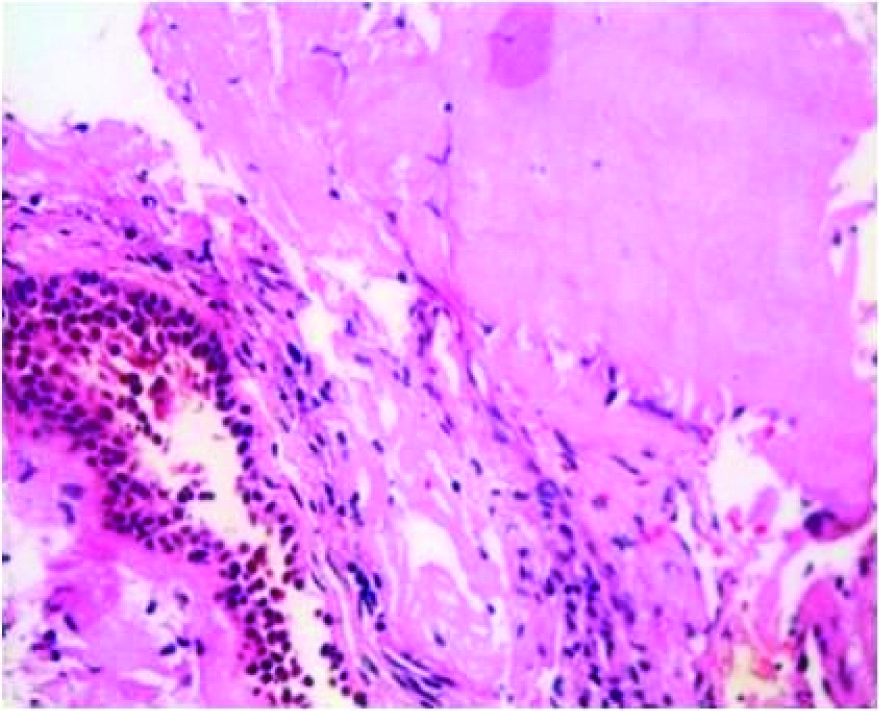

Transbronchial lung biopsy was done and showed subepithelial deposits of acellular eosinophilic homogenous material resembling amyloid [Table/Fig-3]. Some of these deposits formed casts surrounded by inflammatory cells composed of lymphocytes, histiocytes and multinucleate giant cells [Table/Fig-4].These deposits showed apple green birefringent under polarising microscopy using Congo red stain [Table/Fig-5]. Thioflavine T stained the deposits. On immunohistochemistry Lambda light chain antibody intensely stained the deposits [Table/Fig-6]. Kappa light chain antibody was negative.

Some of these deposits formed casts surrounded by inflammatory cells and multinucleate giant cells,H&E 400x magnification